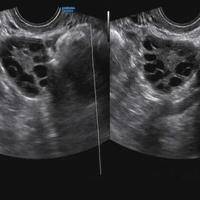

试管治疗前卵泡大小不均匀不能进促排周期吗?

问题描述:我昨天去做了试管治疗前的咨询和详细检查,从结果来看显示我的卵泡大小不一。我看治疗要先做促排,但我担心卵泡无法正常发育成熟所以想问问这个情况下是不是不能进促排周期啊?最佳回答:可以进促排周期。基础卵泡大小不一致是一个比较常见的情况,这是由于卵巢反应不同所引起的情况。针对这种情况,医生会根据每个人的具体身体情况进行个性化治疗,选择合适的促排卵方案,以此来获取到成熟且数量足够的卵泡用于试管治疗...